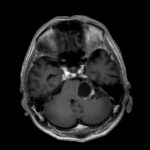

断層撮影

手術前1

手術前2